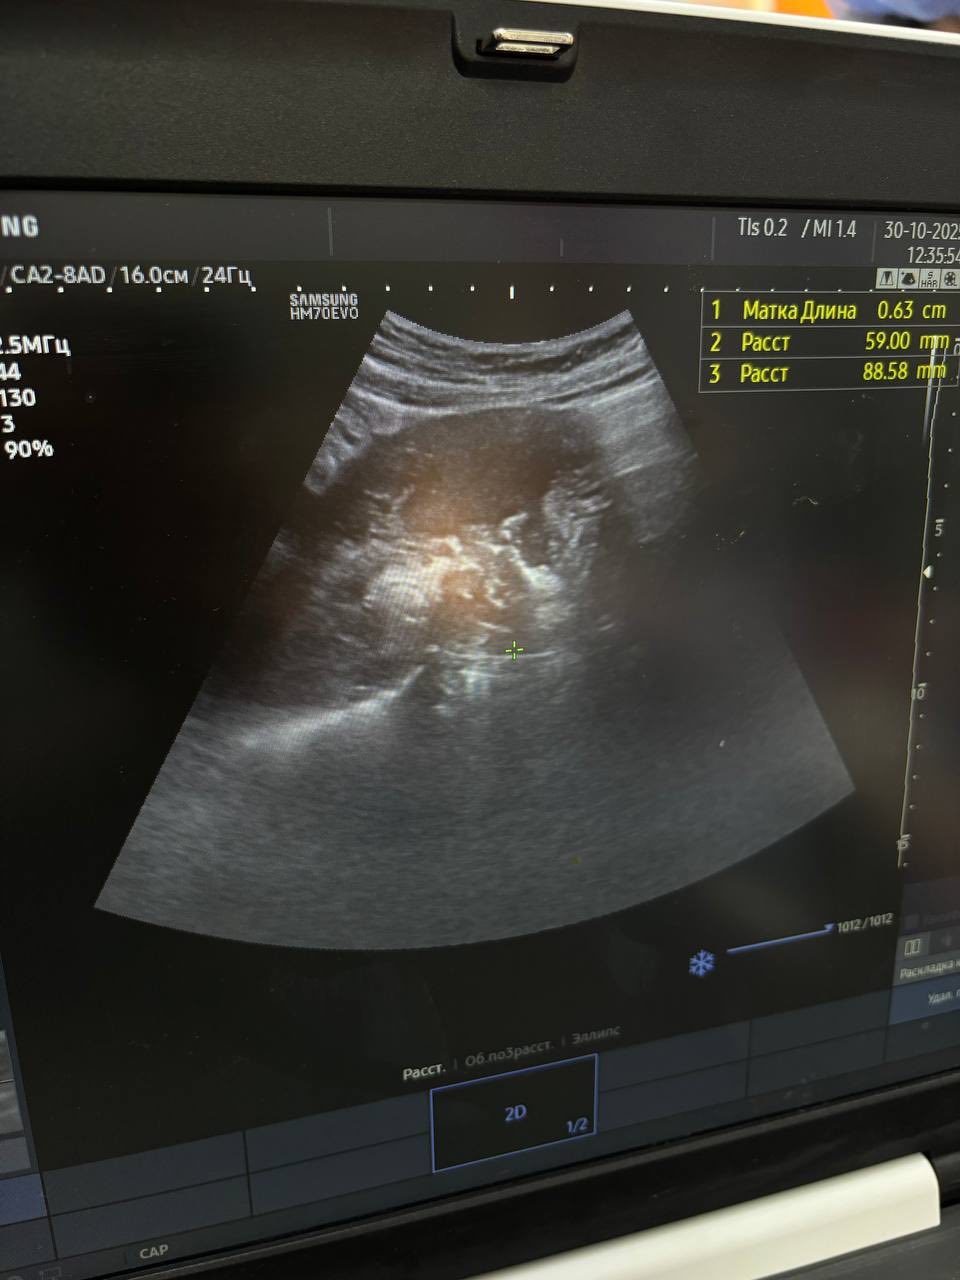

До Вінницької обласної клінічної лікарні ім. М. І. Пирогова 18-річна дівчина поступила з матковою кровотечею. Чотири місяці тому вона народила свою першу дитину.

«В анамнезі серйозні хвороби: епілепсія з частими нападами, хронічний гепатит С, лімфобластний лейкоз у минулому, ураження лімфовузлів і сирінгомієлія з ураженням лівої тім’яної ділянки головного мозку. Стан був загрозливим: кровотеча могла стати фатальною. Але синхронна команда гінекологів, анестезіологів та інтервенційних хірургів діяла злагоджено й швидко», – йдеться у повідомленні.

Було проведено два втручання одномоментно:

Емболізацію судин матки – аби зупинити кровотечу без видалення органа.

Гострий кюретаж з евакуацією вмісту порожнини матки – для очищення порожнини матки після стабілізації кровотоку.

«Таке поєднання дозволило зберегти не лише життя, а й репродуктивну функцію. Дівчина має шанс у майбутньому знову стати мамою.

Коли кожна хвилина – вирішальна, лише командні дії здатні врятувати життя. У цій історії – професіоналізм, точність і людяність, які створюють диво медицини», – йдеться у повідомленні.